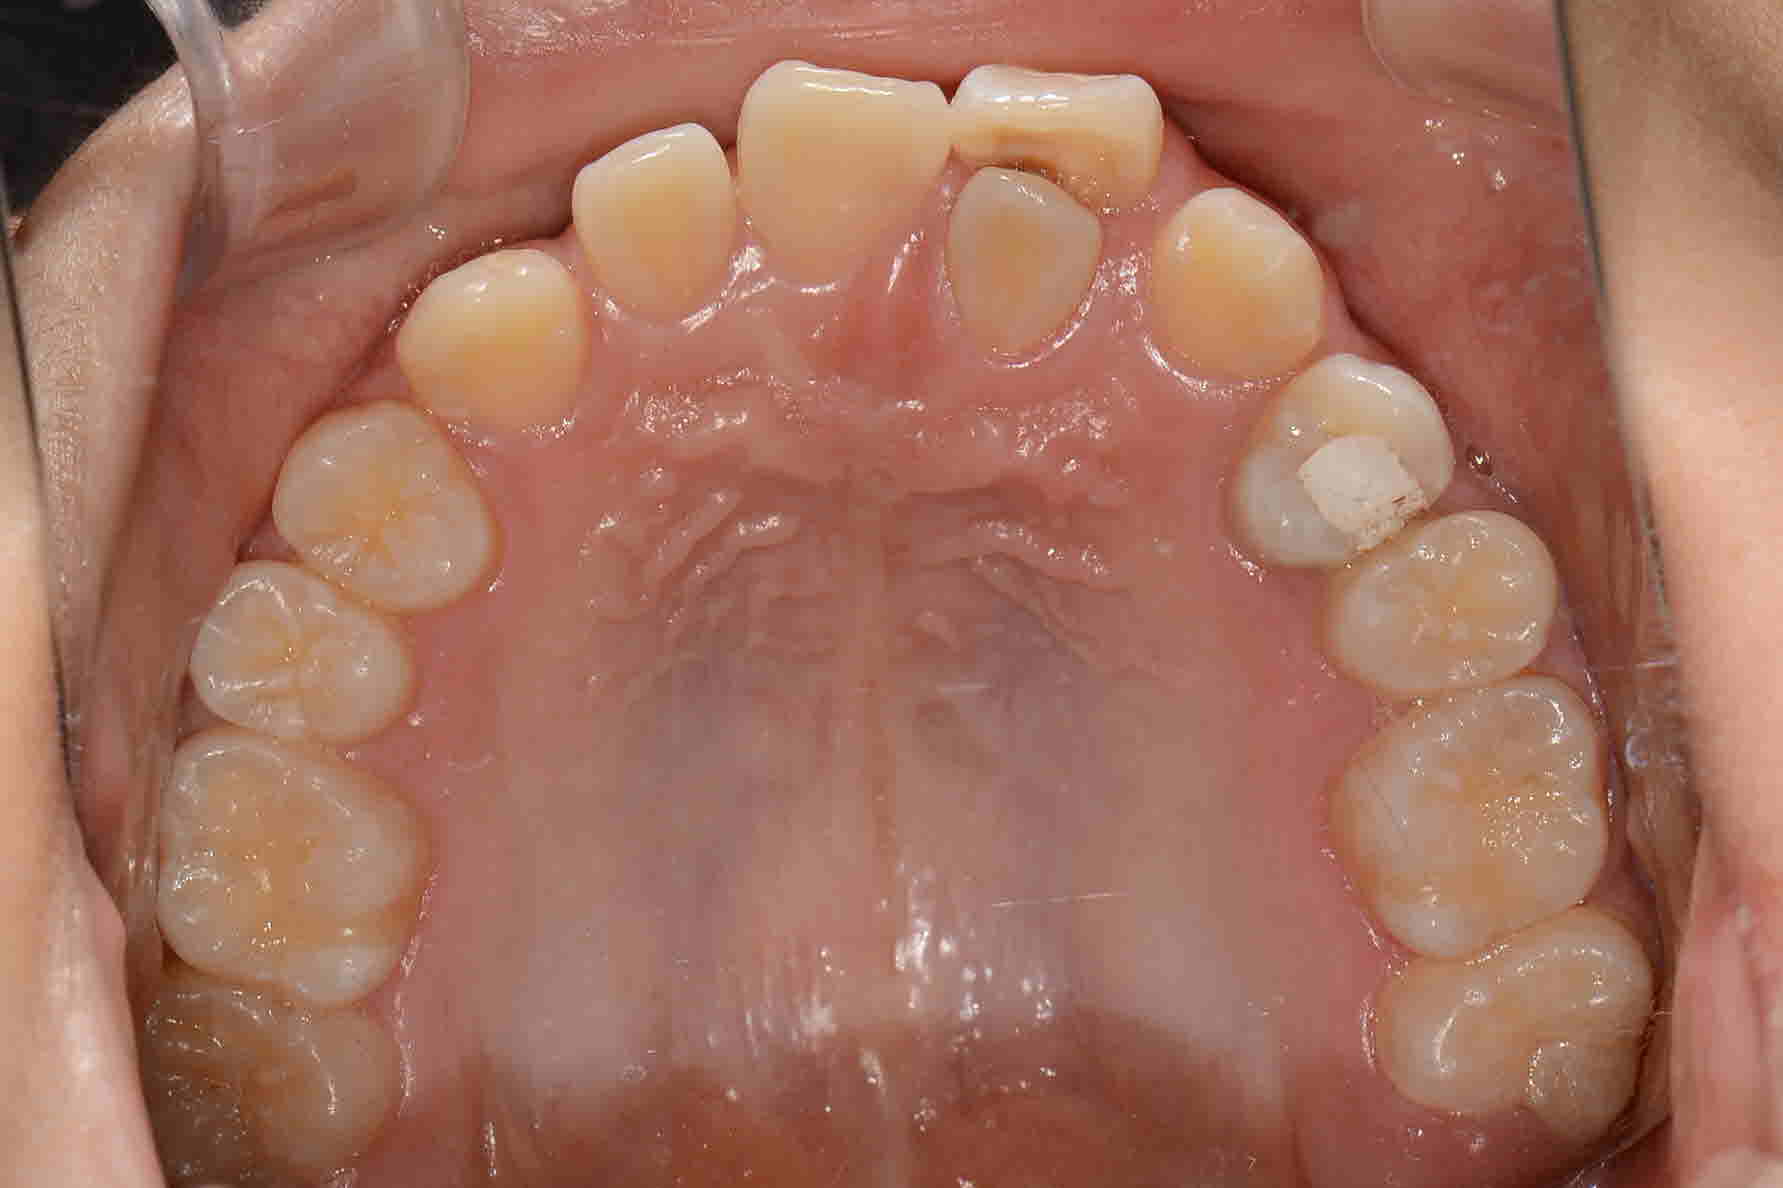

2017년 7월 교합면

2018 년 9월 교합면

2019년 6월 교합면